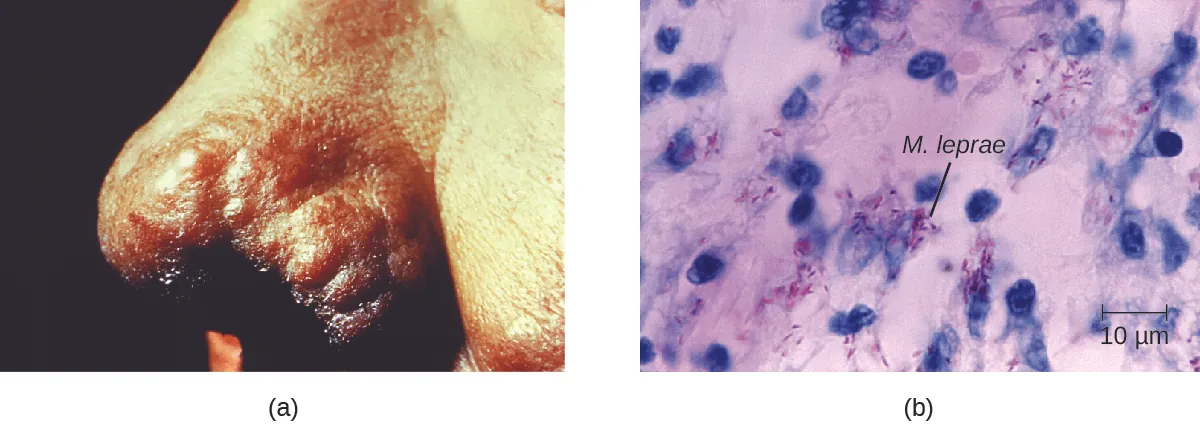

The extent of the disease is related to the immune response of the patient. Initial symptoms may not appear for as long as 2 to 5 years after infection. These often begin with small, blanched, numb areas of the skin. In most individuals, these will resolve spontaneously, but some cases may progress to a more serious form of the disease. Tuberculoid (paucibacillary) Hansen’s disease is marked by the presence of relatively few (three or less) flat, blanched skin lesions with small nodules at the edges and few bacteria present in the lesion. Although these lesions can persist for years or decades, the bacteria are held in check by an effective immune response including cell-mediated cytotoxicity. Individuals who are unable to contain the infection may later develop lepromatous (multibacillary) Hansen’s disease. This is a progressive form of the disease characterized by nodules filled with acid-fast bacilli and macrophages. Impaired function of infected Schwann cells leads to peripheral nerve damage, resulting in sensory loss that leads to ulcers, deformities, and fractures. Damage to the ulnar nerve (in the wrist) by M. leprae is one of the most common causes of crippling of the hand. In some cases, chronic tissue damage can ultimately lead to loss of fingers or toes. When mucosal tissues are also involved, disfiguring lesions of the nose and face can also occur (Figure 26.11).

Hansen’s disease is diagnosed on the basis of clinical signs and symptoms of the disease, and confirmed by the presence of acid-fast bacilli on skin smears or in skin biopsy specimens (Figure 26.11). M. leprae does not grow in vitro on any known laboratory media, but it can be identified by culturing in vivo in the footpads of laboratory mice or armadillos. Where needed, PCR and genotyping of M. leprae DNA in infected human tissue may be performed for diagnosis and epidemiology. Chemist Alice Ball, at the relatively young age of 23, developed the first effective method for treating Hansen's disease. Oil from the chaulmoogra tree had been shown to impact the disease, but the substance was extremely thick and viscous, rendering it unusable as an injectable treatment. Ball recognized that the oil's ester compounds were critical to counteracting the bacteria, so she created a method to isolate the esters using alcohol, and after further manipulation created a water soluble version. Ball unfortunately passed away a year later, and the university president fraudulently published her work as his own; however, a local surgeon who had collaborated with Ball repudiated those claims. The "Ball Method" was used to create the first widely effective treatments, and the chaulmoogra-based medicine was the primary global treatment for leprosy until sulfone therapies were developed in the 1940s.

a) Black tissue on end of nose. B) Small purple cells next to larger blue ones.

Figure 26.11 (a) The nose of a patient with Hansen’s disease. Note the lepromatous/multibacillary lesions around the nostril. (b) Hansen’s disease is caused by Mycobacterium leprae, a gram-positive bacillus. (credit a, b: modifications of work by the Centers for Disease Control and Prevention)